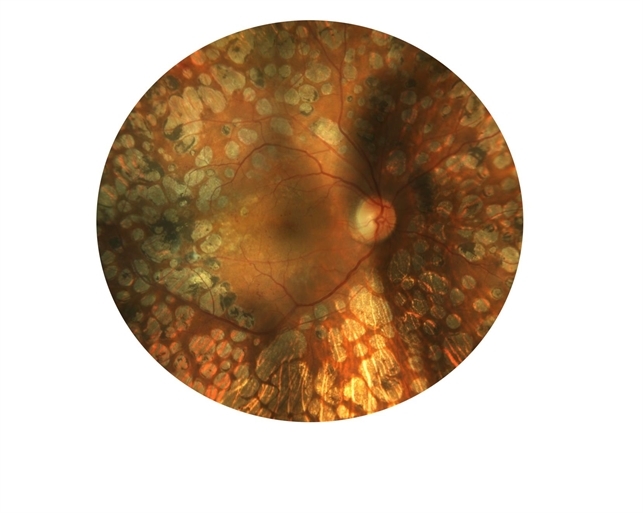

- proliferative diabetic retinopathy (PDR)

- 50-year-old diabetic lasered for proliferative diabetic retinopathy and is holding on well since 10 years.